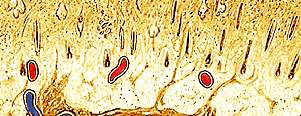

Diploe.jpg

Lámina exterior

Diploe

Lámina interior